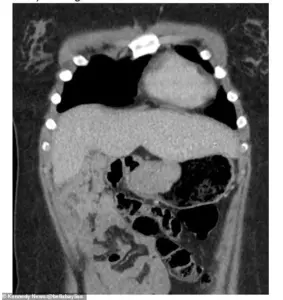

The medical team performed an endoscopy, a procedure that involves inserting a thin, flexible tube with a camera through the throat to examine the upper digestive system.

What they found was nothing short of shocking: a 6cm gastrointestinal tumor (GIST) nestled deep within her stomach. ‘I went home and a few months later I went back because I was anaemic again and I had an endoscopy and that’s when they found the tumour in my stomach,’ she said. ‘If they hadn’t have left me for so long I wouldn’t have had to have that much of my stomach removed because the tumour got bigger within that time.’

GIST, or gastrointestinal stromal tumors, is an exceptionally rare form of cancer that affects only 10-15 people per million annually.

The surgery to remove the tumor was both necessary and life-altering.

Surgeons had to remove 70 percent of her stomach, a decision Bella believes could have been avoided if her initial concerns had been taken seriously.